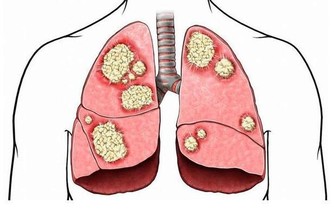

維生素B9的這種天然形式存在於綠葉蔬菜,堅果,豆類和其他食品中。孕婦採用實驗室製造的稱為葉酸的維生素B9,以幫助預防嬰兒出生缺陷。葉酸有助於細胞生長,並可以預防中風和某些癌症了。食物中的葉酸是安全的。但是,補品或強化食品中的葉酸過多會增加患結腸癌或神經損傷的機率。